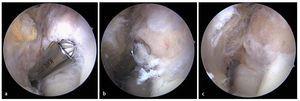

Fig. 8 a) Mediante un artroscopio estándar (ángulo visual de 30º) es posible visualizar el compartimento anterior. Primero se observa el húmero distal (1), la cabeza del radio (2) y el tejido sinovial (3). b) A continuación se desplaza el artroscopio más hacia el interior del compartimento anterior. Aquí se pueden observar la tróclea humeral (1), el proceso coronoides (2) y el tejido sinovial (3). Con frecuencia se observan osteofitos (4) en la zona del húmero anterior, así como cuerpos articulares libres (5).

Fig. 9 La perforación del abordaje anteroulnar se realiza mediante una aguja canulada. a) Bajo visión artroscópica desde anteroradial se realiza en primer lugar la punción con la aguja en el portal anteriormente marcado. b) Si la aguja está correctamente posicionada, tras la incisión cutánea se procederá al corte romo con tijeras del tejido subcutáneo y de la cápsula. c) A través de este portal se introducirá a continuación un resector sinovial motorizado. A través del portal anteroulnar se puede quitar la membrana sinovial inflamada.

Fig. 10 Después de la sinovialectomía se extraen los cuerpos articulares libres. Según el tamaño de estos cuerpos, la extracción se realizará mediante pinzas o un resector sinovial.